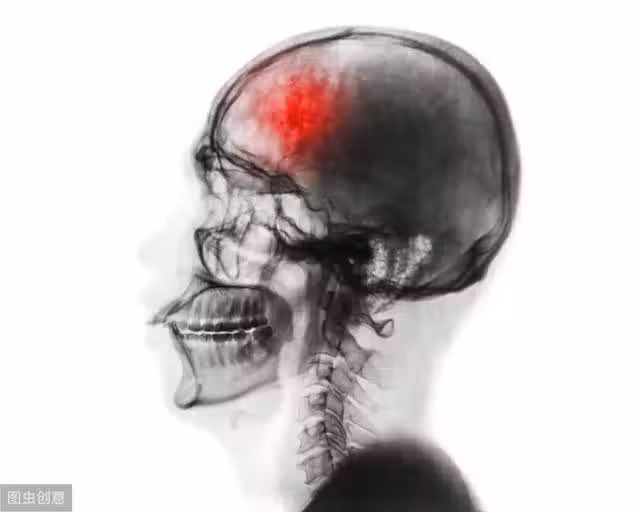

這個病連醫生都很容易得!5大徵兆中了一個,十有八九是腦中風!

腦中風的5大徵兆不可輕忽

以上說的這兩種輕微中風,雖然症狀很快就會消失,但卻是未來可能發生更嚴重腦中風的先兆,醫生預估再次發生中風的幾率一般人的4到5倍,所以必須嚴加註意。

有關部門的一項調查結果顯示,65歲以上的國人有11.6%疑似發生過小中風,40到64歲人也有3.41%疑似發生過小中風,但竟然有37%的人沒有做進一步的檢查

近70%的人沒有做體重控制,顯示人們不重視小中風的威脅。